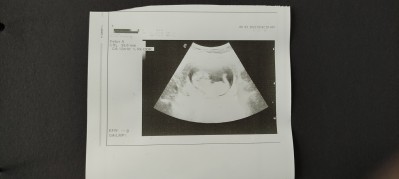

13+4

Ben kız hissediyorum ama sizce cinsiyeti nedir doktor henüz bir şey demedi ama belki de 3 lü testte net belli olur.. sizin fikirleriniz nedir?imageBirde hanımlar bu dönemlerde belime bıçak saplanıyor sanki. Ayakta durmayı geçiyorum uzanamıyorum bile. Sizde de böyle oluyor mu? Sizce karnımızın büyümesinden mi kaynaklı?

Gebelik haftası 13+4